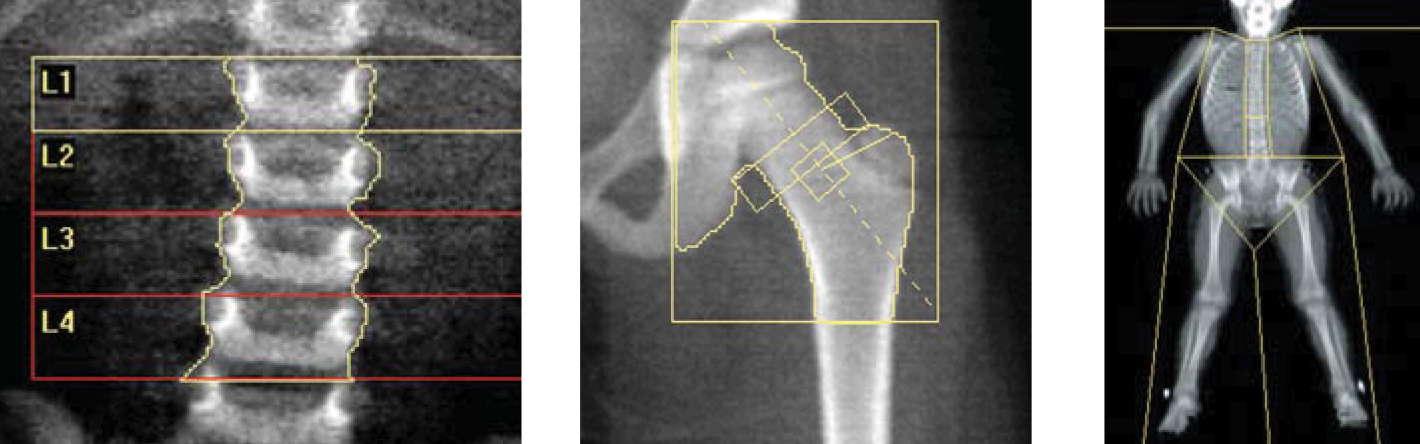

Kemik mineral yoğunluğunu ölçmek için yapılan teste kemik dansitometri denir. Kemik yoğunluğu ölçümü için günümüzde en çok kullanılan yöntemdir.

Kemik yoğunluğu ölçimi çok kolay bir işlemdir.Kişi sırt üzeri yatarken sistem 8 dk.gibi kısa bir sürede ölçümü gerçekleştirmektedir. Kliniğimizde kemik yoğunluğu ölçümü son teknoloji General Electric/LUNAR markacihazımızda yapılmaktadır.

En önemli tanı yöntemi kemik yoğunluğu ölçümüdür. İnceleme çok düşük dozda röntgen ışını kullanılarak özel bir cihozla yapılır. İşlem ön hazıriık veya ilaç gerektirmez, kısa sürer.

Kemik yoğunluğu ölçümü ünitemizde bilgisayar desteğinde hiçbir ön hazırlık yapılmadan, hiçbir enjeksiyon yapılmadan 10-20 dakikada yapılmaktadır.